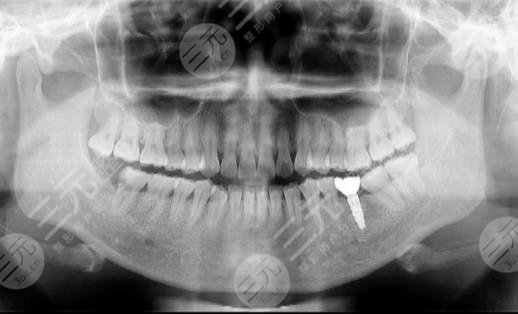

Because the overall condition of my teeth is okay, but it is a little loose, and then the doctor first did an overall examination of my teeth, took a film to determine that I can carry out dental implant surgery, and then set up the plan for me, before the implant first carried out a detailed situation of my teeth, and then the installation of implants, because there is anesthesia, so I don't feel anything, but I can feel that I am doing something on the bone, and it will take about 2 months to carry out the next step after the installation.

Can you take a look at how I looked after the dental implant surgery, is it still relatively good? It looks very natural, and the more important thing is to become particularly strong, like the foods that I didn't dare to eat because of tooth problems before, and I can eat the big bones I like to eat every day, and I am really happy in my heart.